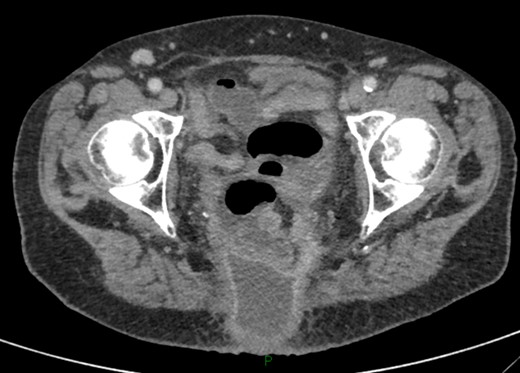

On examination, she was febrile. Her abdomen was generally tender. Bowel sounds were present and up to that time her stoma was working. Her perineal hernia was red and tender. Her initial CXR (Fig. 1) did reveal a sliver of gas underneath her right hemidiaphragm and in keeping with her abdominal findings she progressed to further imaging. CT abdomen pelvis with contrast showed pneumoperitoneum (Fig. 2) with ‘a tiny pocket of air is also seen adjacent to a loop of bowel in the pelvis posterior to the bladder’. ‘Exact site of perforation has not been demonstrated but could possibly be in the bowel loops in the perineum’ (Figs 3 and 4).

CT showing small bowel loops in pelvis with perineal hernia and free fluid.

Sagittal view showing small bowel loops in pelvis with perineal hernia.